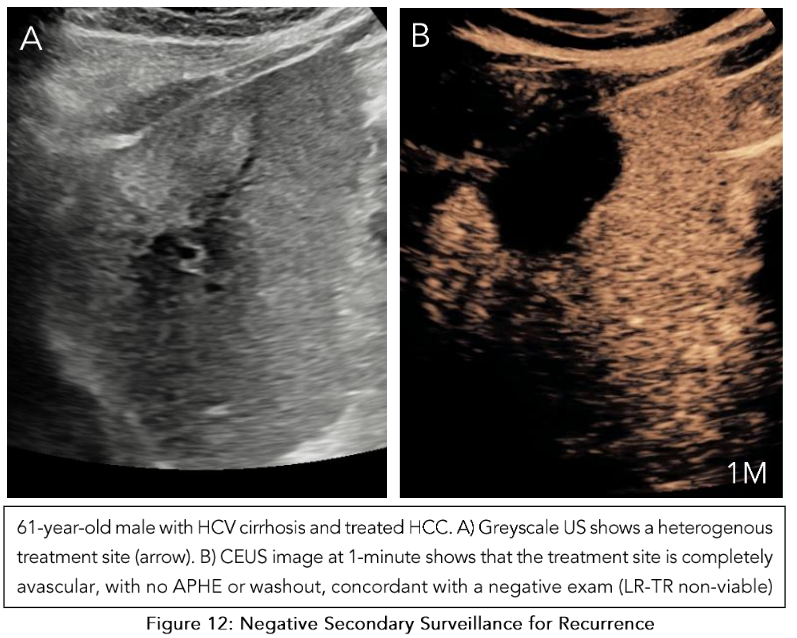

Perilesional viability:

Absent viability is characterized by homogeneous enhancement of the ablation margins compared to the rest of the liver. Uncertain viability is characterized by arterial phase hyperenhancement without washout, isoenhancement with washout, or hypoenhancement. The presence of a viable tumor is confirmed by hyperenhancement with washout (Figure 11). Once both these categories are assessed, an overall treatment response score is determined based on their respective contributions:

If there is any intralesional or perilesional viability, the overall treatment response score is LR-TR viable.

If there is any uncertainty in one without viability present in the other, the overall treatment response score is LR-TR equivocal. Here, an alternative imaging modality like MRI would be useful in clarifying the viability.

Only when there is absent viability in both intralesional and perilesional viability is the final category designated as LR-TR nonviable (Figure 12).